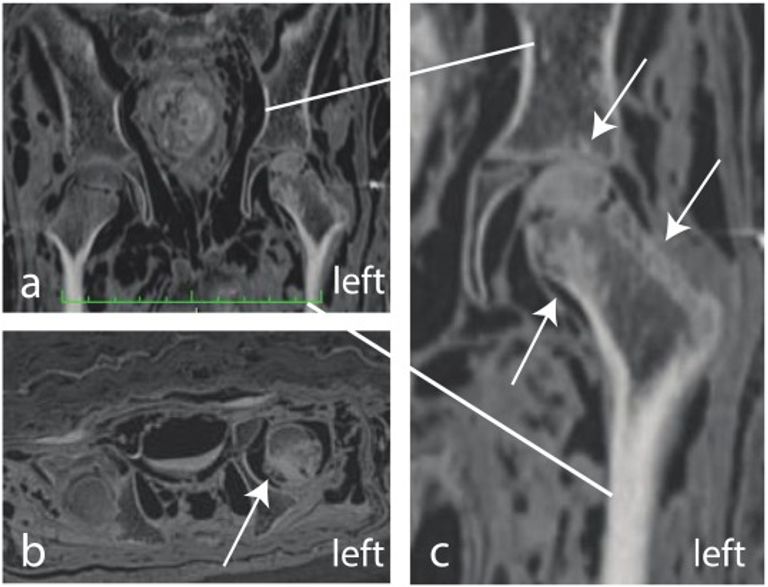

وفي دراسة نُشِرت تفاصيلها مؤخراً بدورية العلوم الأثرية "Journal of Archaeological Science"، تمَّ إخضاع المومياء للتصوير المقطعي والأشعة السينية التي كشفت عن إصابة صاحبها بآفات عظميّة صلبة متعددة البؤر تؤثِّر على العمود الفقري والورك الأيسر.